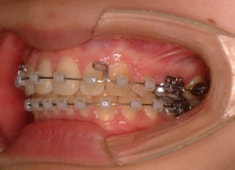

治療法:表の矯正(T21ブラケット)

治療開始時